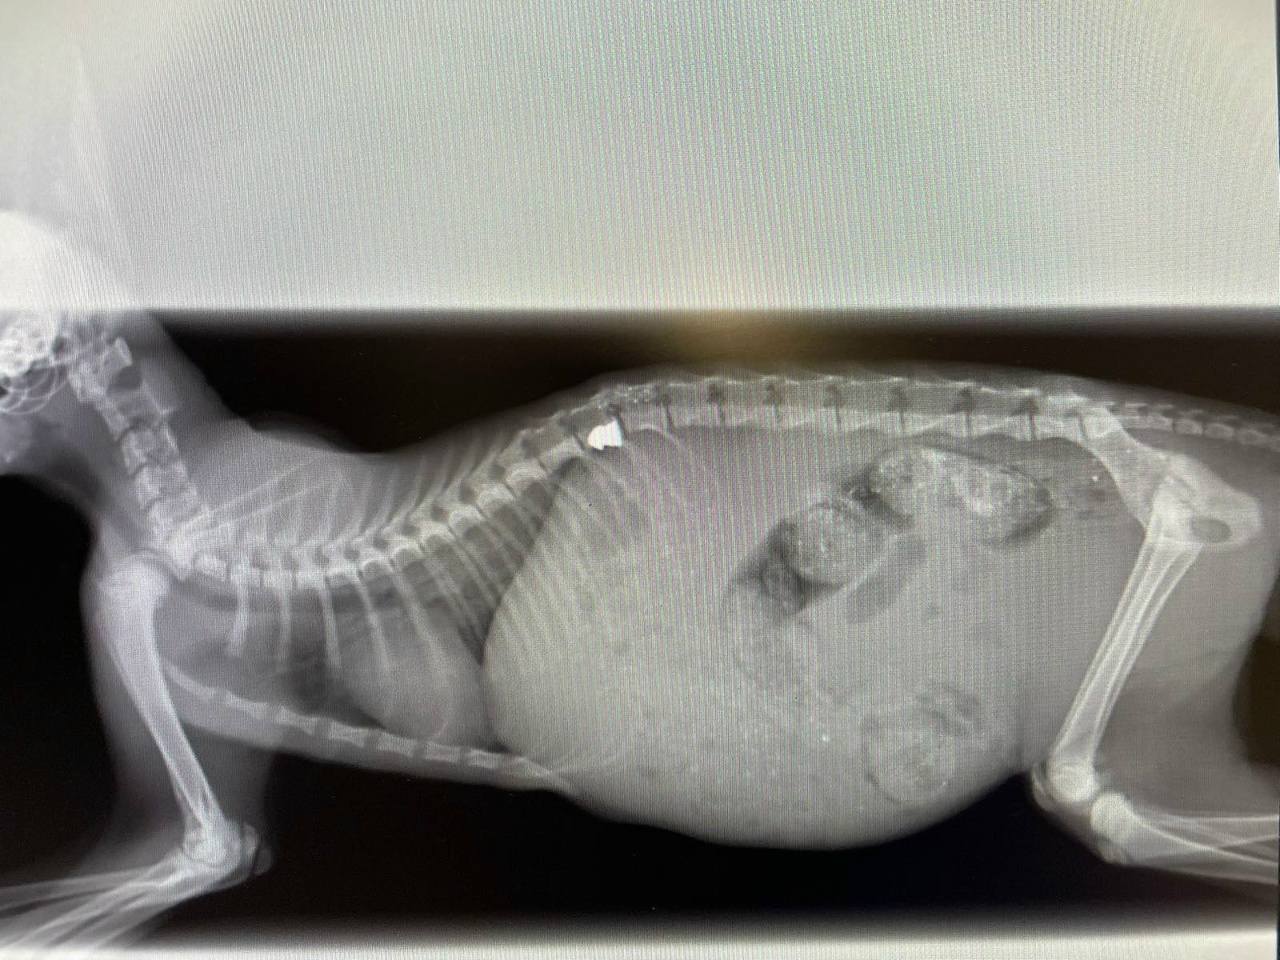

Специалисты ветклиники провели котёнку необходимую диагностику, включая МРТ, а также сделали операцию по извлечению пули. К несчастью, позвоночник был задет и повреждены нервные окончания, поэтому задние лапы животного отказали.